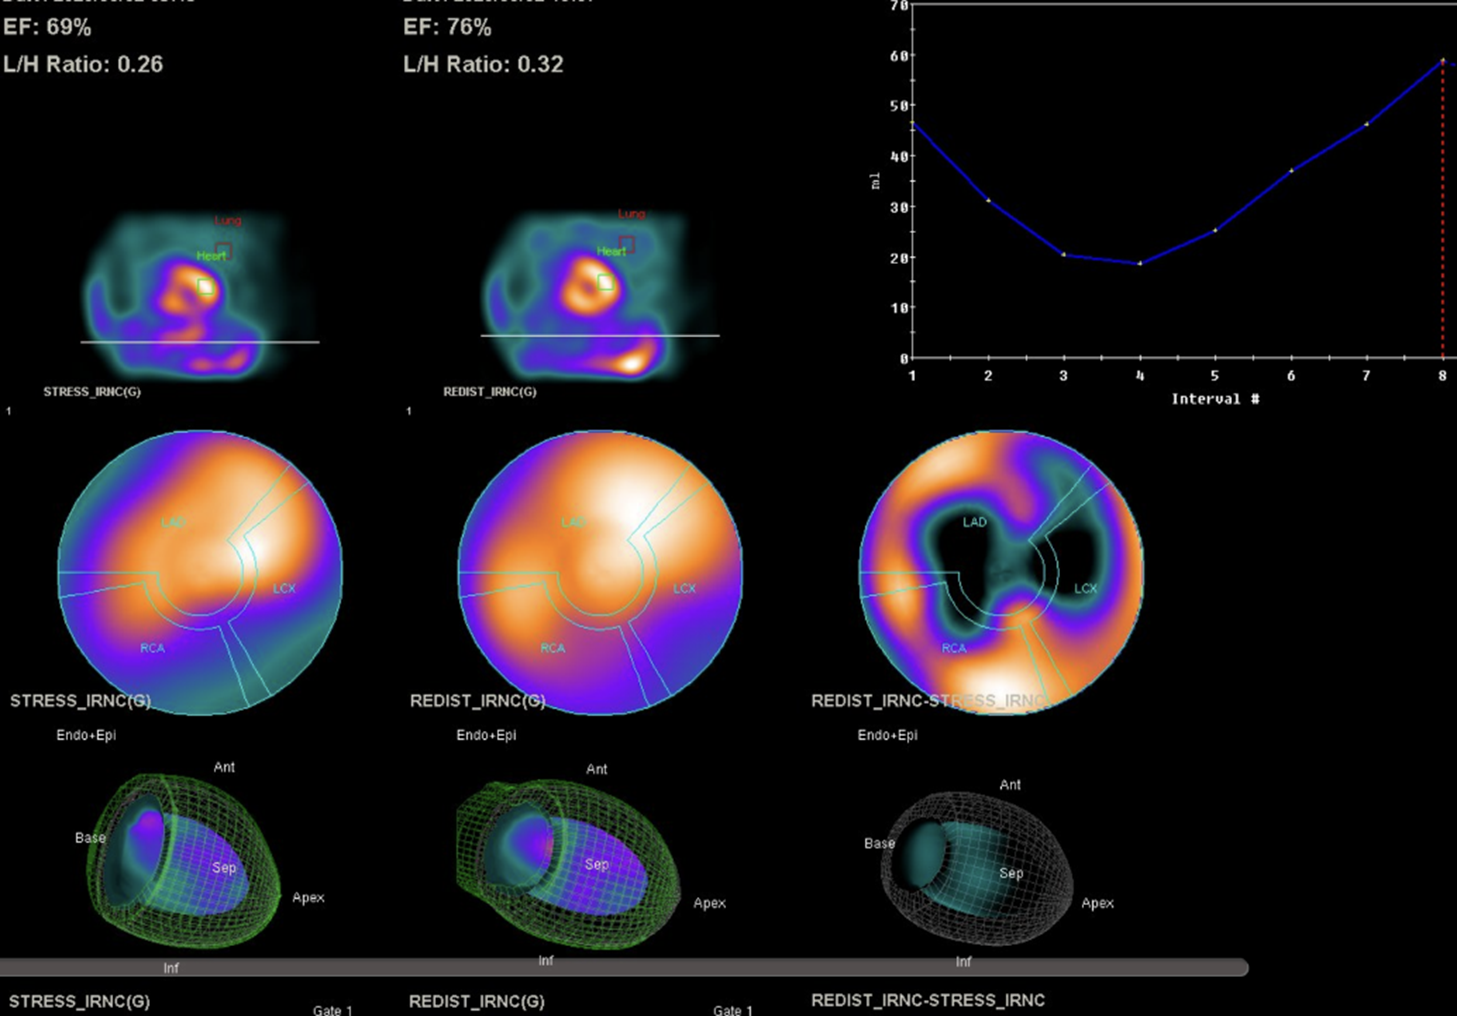

The laboratory test showed white blood cell count (WBC) of 7.8x10^3/uL, hemoglobin (Hb) level of 15.1gm/dl, platelet count of 181x10^3/uL.The glucose level is 98mg/dL, The liver enzyme levels show GOT (AST) at 19 U/L and GPT (ALT) at 22 U/L. Lipid panel results include HDL-C at 44mg/dL, LDL-C at 62mg/dL, triglycerides at 101mg/dL.Creatinine level of 0.75 mg/dL (eGFR:108.53) Tl-201 myocardial perfusion scan showed abnormal uptake in inferior, inferolateral, and septal wall

Right coronary artery: very large, long dominant RCA, supplying inferior and lateral wall, middle segment total occlusionWe referred him to cardiovascular surgeon for CABG evaluation but he refused and preferred PCI

Right coronary artery: very large, long dominant RCA, supplying inferior and lateral wall, middle segment total occlusionWe referred him to cardiovascular surgeon for CABG evaluation but he refused and preferred PCI